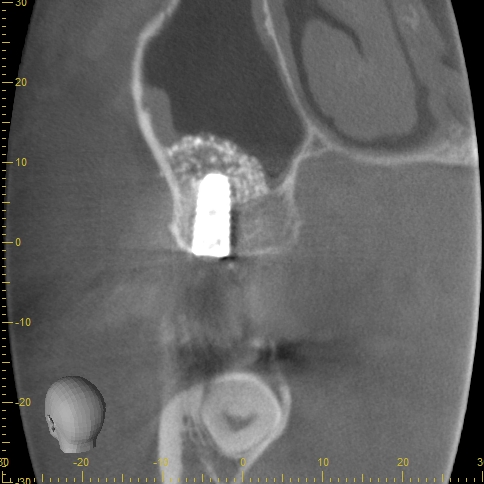

毎週水曜日は笹尾歯科医院・ササオインプラントセンターではオペを行っています。午前一人・午後一人のみ行います。時間に余裕を持つことにより、クロスコンタミネントの予防・院内感染の予防・偶発症に対処する事ができます。また、麻酔専門医による全身管理、セデーションも行っております。 本日は、ラテラルスリット…